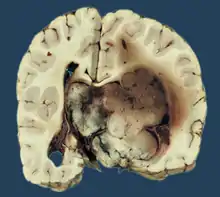

Choroid plexus papilloma, also known as papilloma of the choroid plexus, is a rare benign neuroepithelial intraventricular WHO grade I lesion found in the choroid plexus.[1] It leads to increased cerebrospinal fluid production, thus causing increased intracranial pressure and hydrocephalus.[2]

Choroid plexus papilloma occurs in the lateral ventricles of children and in the fourth ventricle of adults. This is unlike most other pediatric tumors and adult tumors, in which the locations of the tumors is reversed. In children, brain tumors are usually found in the infratentorial region and in adults, brain tumors are usually found in the supratentorial space. The relationship is reversed for choroid plexus papillomas.

Choroid plexus tumors are divided into three categories by the World Health Organization (2016):[9] papillomas (grade I), atypical tumors (grade II), and carcinomas (grade III). Less than two mitotic figures per 10 high power fields are present in CPPs, two to five are present in atypical ones, and more than five are present in carcinomas. The tumors are visible as pink, soft, spherical lumps with erratic projections and considerable vascularity.

A neurosonogram via the anterior fontanelle will show an echogenic lesion inside the ventricles if the fontanelles are not united. This lesion exhibits bidirectional flow throughout the diastole, demonstrating blood flow via disorganized vascular arrangement. Sometimes ultrasound scans are used to diagnose the lesions before birth.[15] An isodense or slightly hyperdense lesion inside the ventricles, as well as the resulting ventriculomegaly, are visible on computer tomography (CT).[16] The intraventricular lobulated masses are well-defined and resemble fronds; they are hypointense on T1WI and hyperintense on T2WI on magnetic resonance imaging (MRI).[17] Active blood flow is indicated by the presence of flow voids. A rich vascularity gives the lesions a brilliant enhancing quality. Recent researches have shown that choroid plexus papilloma and choroid plexus cancer may be distinguished from one another using arterial spin labeling.[18]